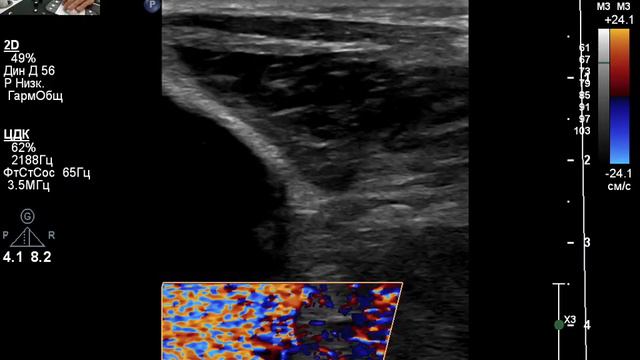

Видео узи артерий

Видео узи артерий 107 фото